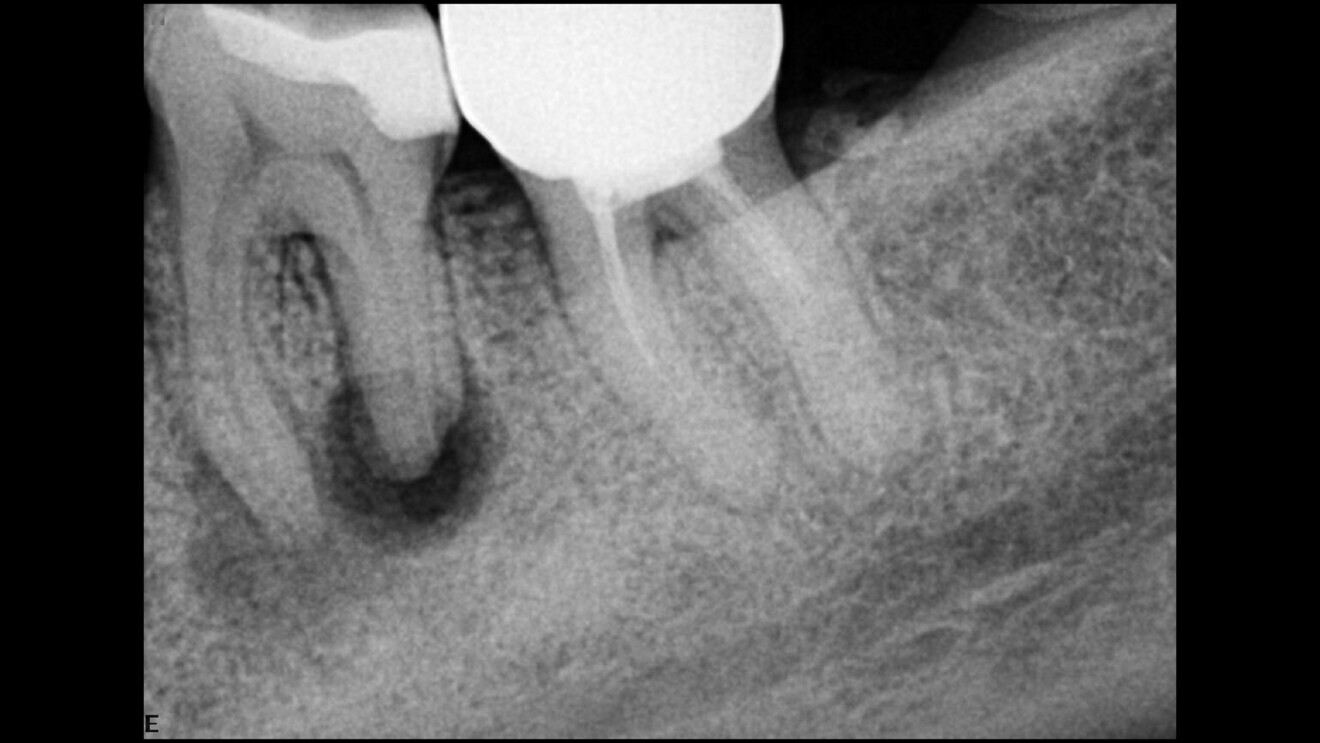

Irrigation in endodontics is widely misunderstood, yet it is so simple when we understand the chemicals that we are using and what our goal is and how to achieve it. By giving each chemical the work or the target that it is supposed to achieve and by understanding chemical interactions—irrigation is a matter of dealing with different kinds of chemicals—we can achieve better, much faster and safer root canal disinfection. Before the use of sodium hypochlorite, it took up to 20–30 minutes, and now it takes seconds. A bacterial level of zero is in our reach, and it does not take rocket science to achieve it. Zero bacteria means that we can have a better prognosis for the root canal treatment and higher success rates for our retreatment as well in a single visit and no temporary dressing needed—the myth of calcium hydroxide is no more. By way of demonstration, consider the case of a necrotic molar with a relatively large radiolucency that we treated with a root canal treatment in a single visit following our irrigation protocol (Figs. 4–6).

Fig. 4: Necrotic molar with a relatively large radiolucency.